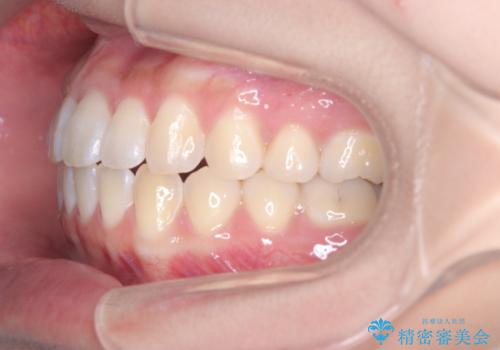

翼状捻転と叢生を矯正で改善

治療では、審美ワイヤーを使用し、目立ちにくく配慮しながら矯正を進めました。上顎にリンガルアーチと矯正用アンカースクリューを用いて臼歯部を安定的に遠心移動させ、歯列全体のスペースを確保しました。その後、回転していた前歯を正しい位置に配列し、全体的な歯並びの改善を行いました。治療中は、装置の適切な管理と口腔衛生を徹底することが重要でした。結果として、見た目だけでなく機能的にも優れた歯列を実現することができ、患者様にもご満足いただけました。